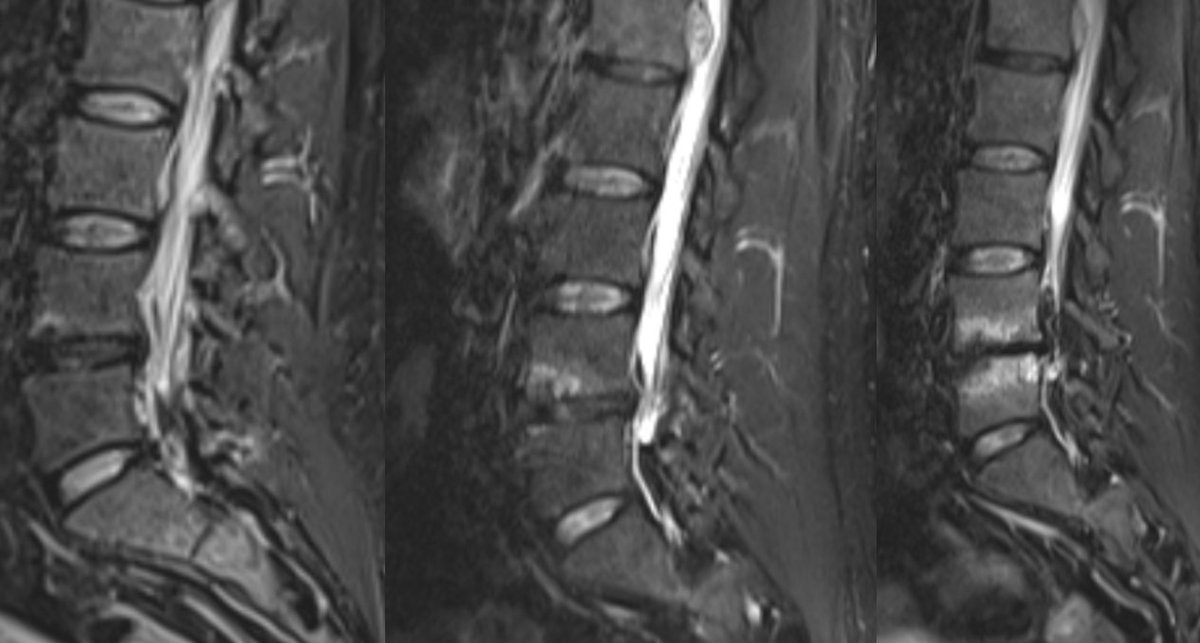

When AI Exposed a Medical Blind Spot – and the Doctors Chose Arrogance A 48-year-old man in Rogaland, Norway, lived with crippling back and leg pain. His doctor sent him to Unilabs, one of Europe’s leading private diagnostic imaging providers, for an MRI scan. Unilabs’ official report concluded that the images showed only “mild degenerative changes.” No clear explanation for his symptoms. The patient was left with nothing.

Gandalv tweet media

@Microinteracti1 I don’t think you need AI to spot the cyst … most on here should be able to spot this - Source. ?